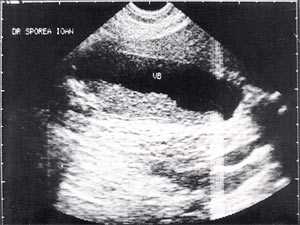

В исследовании, проведенном в США, "желчный сладж" выглядел в виде гиперэхогенного образования в желчном пузыре с горизонтальным уровнем без задней тени, форма которого медленно изменялась при движении больного [10]. Характерный признак "желчного сладжа" - изменение его вида на сканограмме в зависимости от изменения положения тела больного и медленным достижением нового горизонтального уровеня. Общим правилом является отсутствие дистальной акустической тени. Эхогенность сладжа может быть различной. Иногда сладж заполняет весь желчный пузырь, затрудняя дифференцировку между тканью печени и желчным пузырем. Эта ситуация называется "гепатизация желчного пузыря" (рис. 1).

Рис. 1. Гепатизация желчного пузыря, полностью заполненного сладжем.